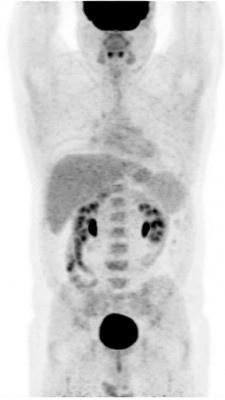

| Патологические очаги при лимфоме | Норма |